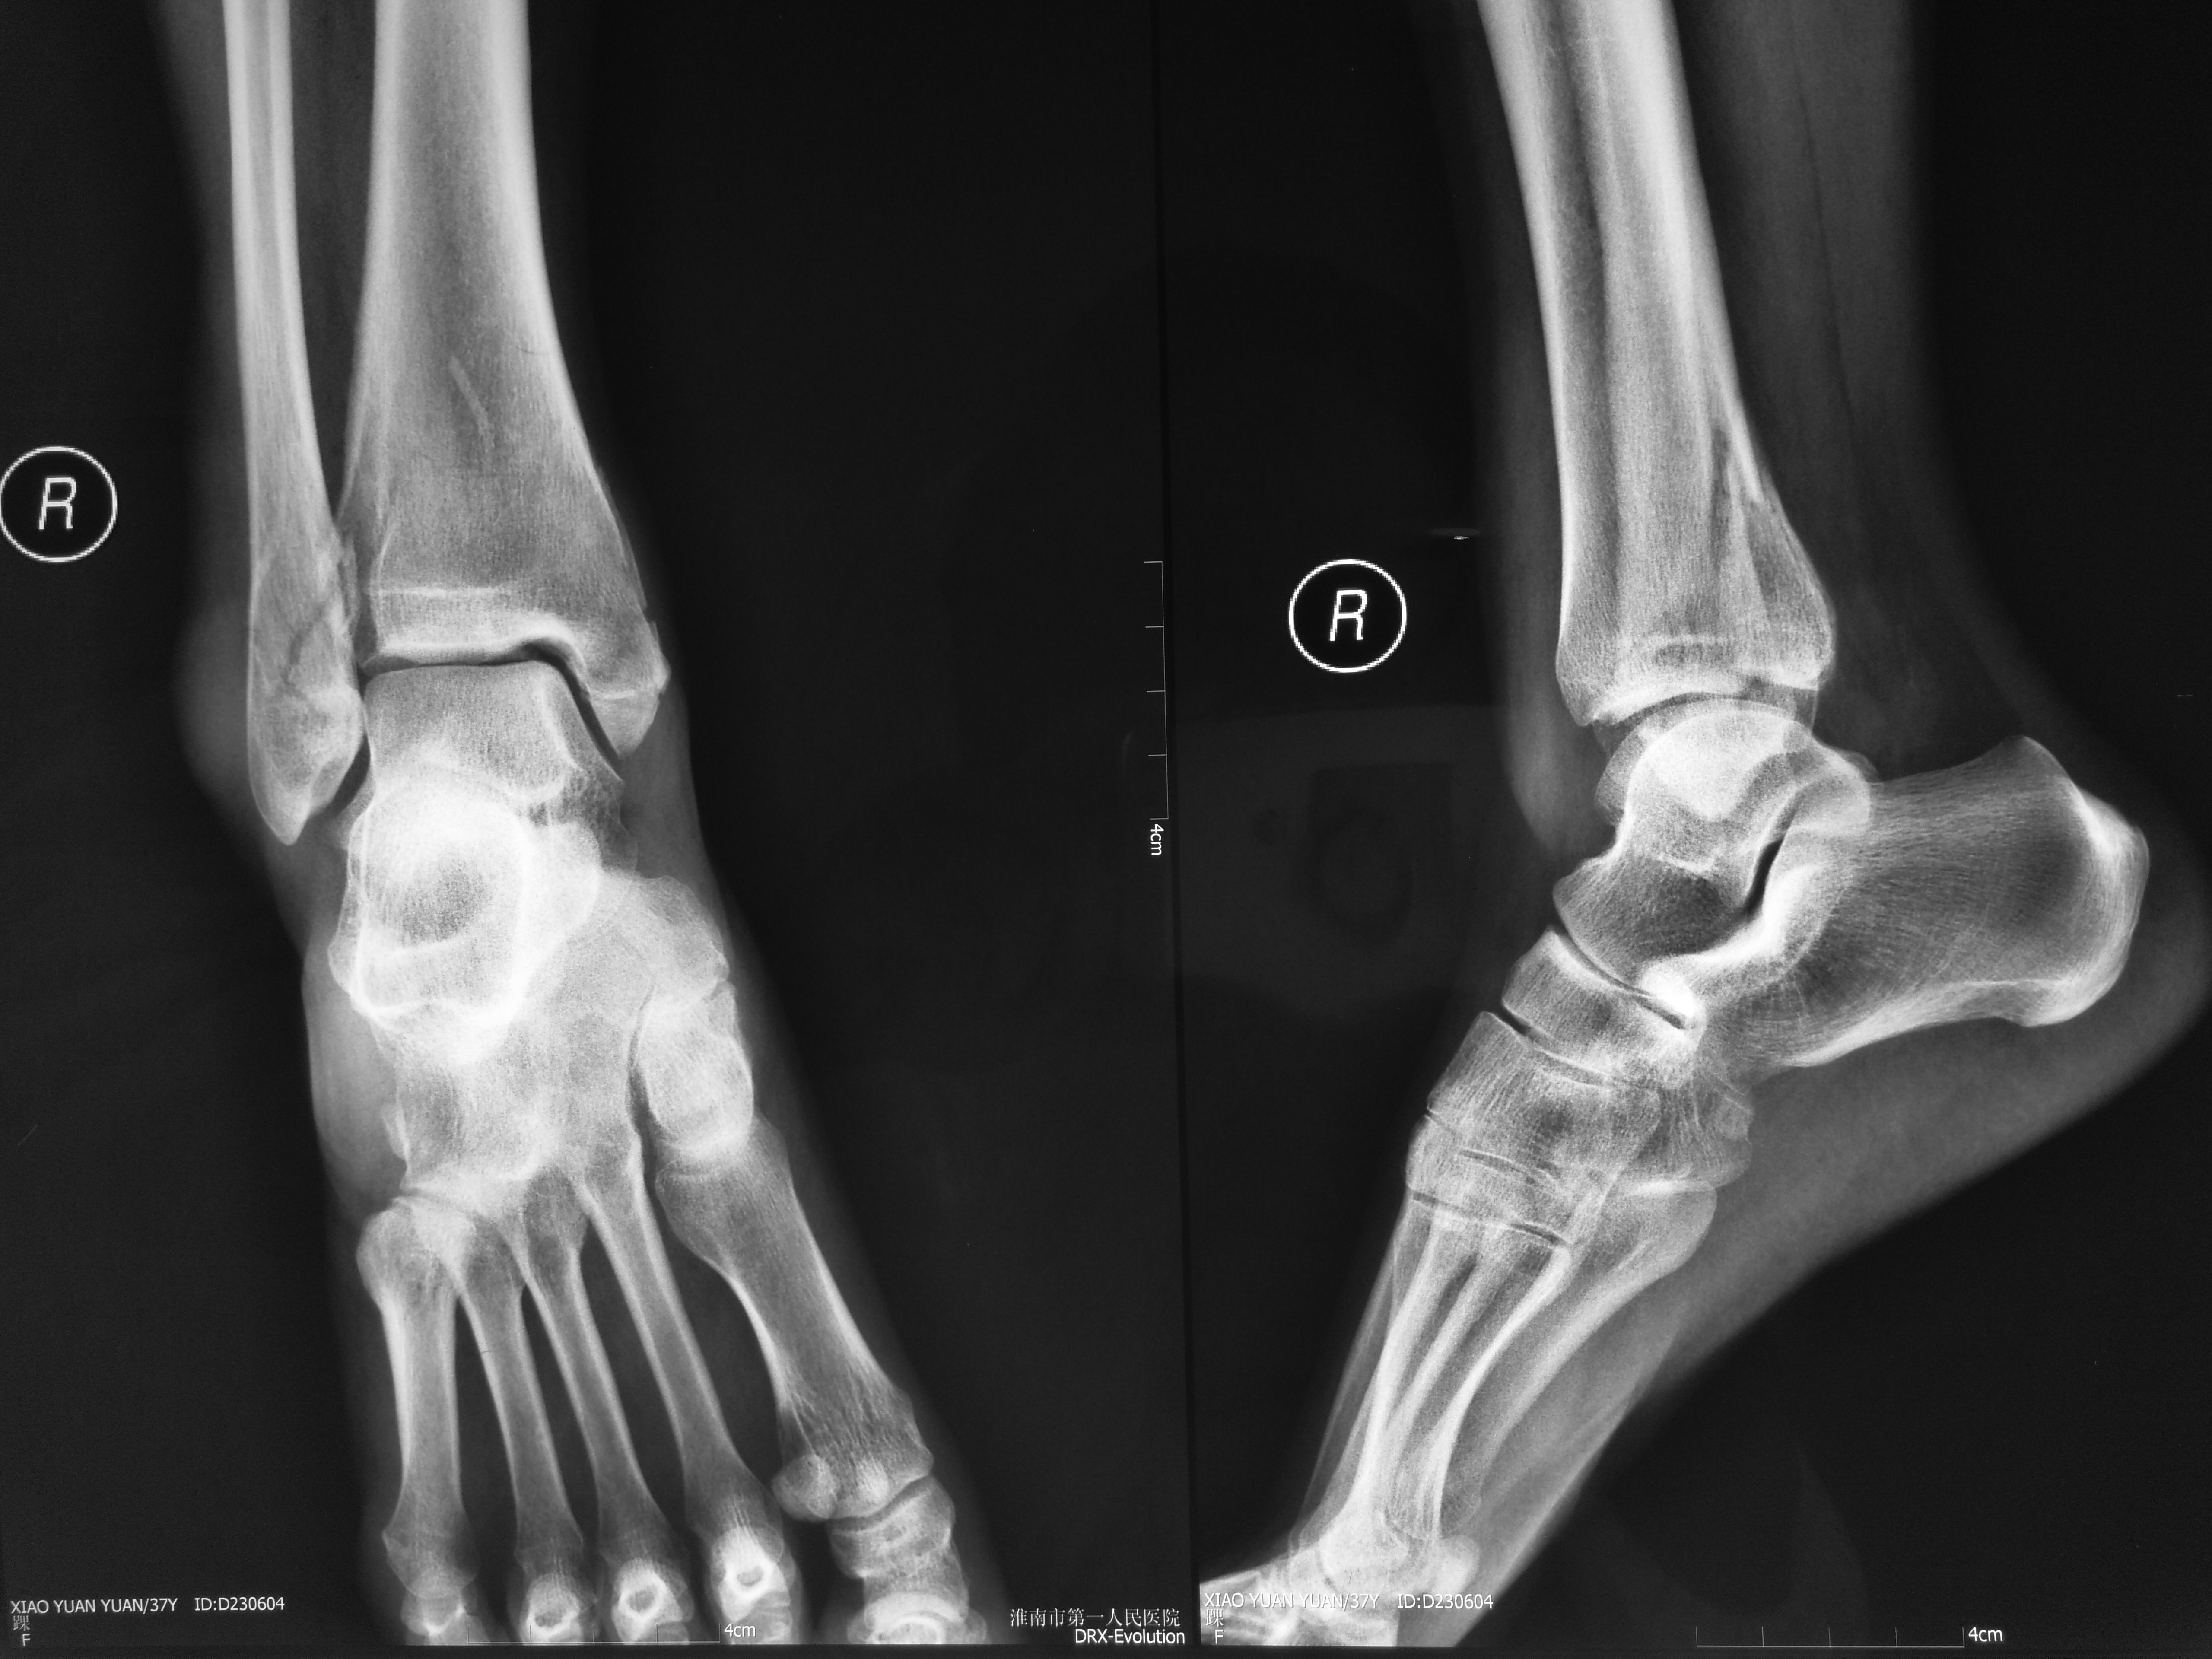

右侧三踝骨折内固定术后骨愈合

图片尺寸546x663